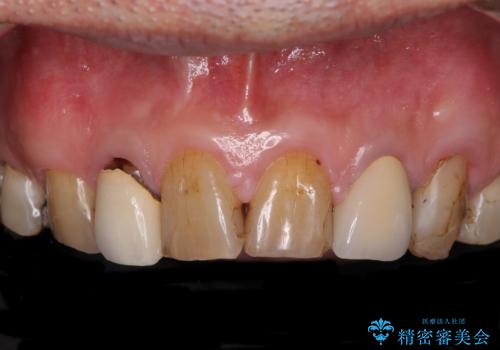

- コンポジットレジンやクラウンなど、様々な医院で治療を受けたために、統一感がなくなってしまった前歯を綺麗にしたいとのことで来院された患者様です。

黄ばんだ前歯や白すぎたクラウン、プラスチックの継ぎ接ぎなどを全てオールセラミッククラウンの統一感のある前歯に仕上げました。